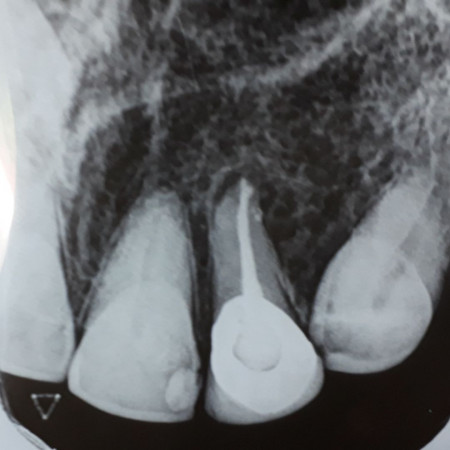

Provision of crowns / onlays to grossly broken-down teeth

When a tooth breaks down due to Dental caries or trauma, it might need a crown or an onlay to preserve the remaining tooth material to keep it for aesthetic or functional purposes. Danthaja specialists will offer you various treatment options considering the remaining tooth substance.

- Full ceramic [Emax] crowns

- Ceramic fused to metal crowns

- Metal crowns